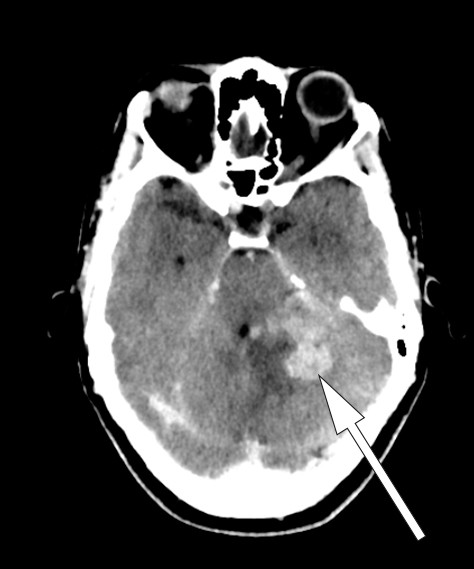

Dag 6 ble hodepinen verre, i tillegg så man parese av n. abducens. Pasienten var vedvarende febril, temperaturen lå mellom 38,0 °C og 38,5 °C. Ny CT caput med kontrast viste kontrastoppladning ved tentoriet, i cerebellum, i pons samt i høyre oksipitallapp med omkringliggende ødem (fig 2). MR cerebrum uten kontrast viste lavt signal på T2-vektet sekvens, tilsvarende de kontrastladende lesjonene (fig 3).

Det ble gjort spinalpunksjon med funn av 182 × 106/l celler (normalt 0–5 × 106/l), glukose 2,1 mmol/l (normalt > 2 mmol/l) og protein 1,38 g/l (normalt 0,15–0,50 g/l), funn vel forenlige med tuberkuløs meningitt. Den tentative diagnosen var dermed miliær tuberkulose med affeksjon av sentralnervesystemet.